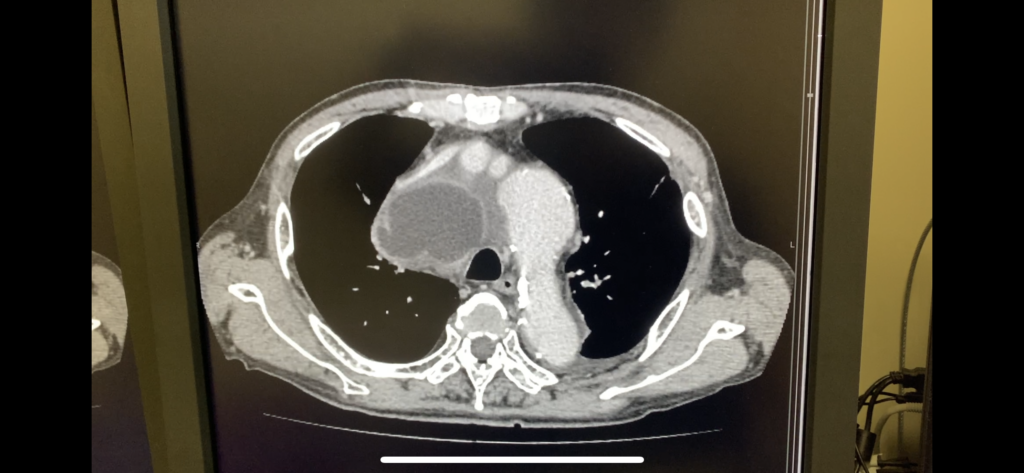

未分類 KNTN病院から大学に送ったこの人は 2023年6月9日 2023年6月9日 Toshi Facebook Twitter Google+ はてブ Pocket Feedly 縦隔膿瘍。DLBCLのケモしたらこうなった。 大学に送ったら明日緊急手術になった。 医局の先生方、ありがとう! キャリアとはこういうことだな。 Facebook Twitter Google+ はてブ Pocket Feedly